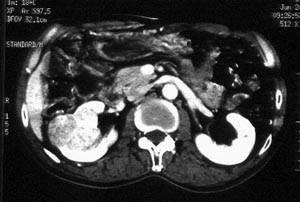

ct平扫加增强扫描:右肾中下极肾盂外侧段实质见分叶状软组织密度肿块,截面大约56x45mm,向外突破肾包膜,向内突入肾盂,平扫密度略不均,ct值32-37hu。c+见病灶不均匀轻-中度强化,内有未强化坏死区。右侧肾周筋膜增厚,右肾内前方见肿大淋巴结。

ct诊断:右肾癌,ct表现见上述,伴同侧腹膜后淋巴结转移。

手术所见:右肾大小15x7cm,背侧有肿物突出肾包膜,大小7x4cm。行“右肾癌根治术”。

手术病理:

透明细胞癌(ⅰ-ⅱ级)